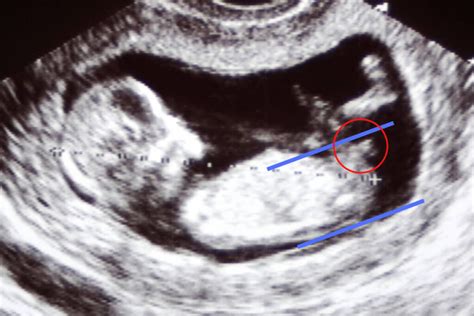

it's a baby girl 🤱by 'Nub Theory' !! Ultrasound

Der Begriff "Nub" stammt aus dem Englischen und bedeutet "Noppe" oder "Knubbel". In der Nub-Theorie bezieht er sich auf den Genitalhöcker (Tuberculum genitale), einen embryonal angelegten Vorsprung im Genitalbereich des Fötus. Dieser entwickelt sich ab der 9. SSW und ist bis zur etwa 14. SSW bei beiden Geschlechtern zunächst ähnlich geformt. Die Nub-Theorie besagt, dass sich anhand der Ausrichtung dieses Genitalhöckers auf dem Ultraschallbild das Geschlecht des Babys vorhersagen lässt.

Die Theorie basiert auf der Betrachtung des Winkels zwischen dem Genitalhöcker (Nub) und der Wirbelsäule des ungeborenen Babys im Ultraschall:

- Jungen: Liegt der Genitalhöcker in einem Winkel von über 30 Grad zur Wirbelsäule und ragt er eher nach oben, soll es sich um einen Jungen handeln.

- Mädchen: Ist der Genitalhöcker hingegen eher parallel zur Wirbelsäule ausgerichtet oder liegt in einem Winkel von unter 30 Grad, soll es sich um ein Mädchen handeln.